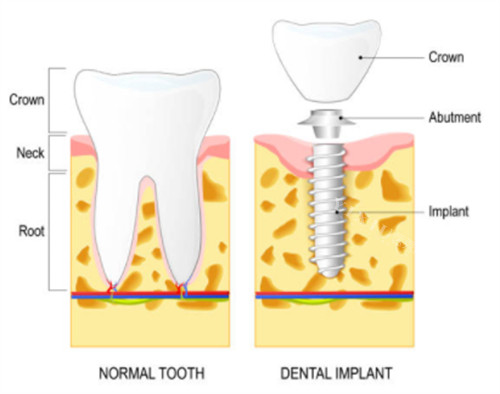

一、种植牙项目

瑞诚口腔采用智能化导板种植技术,误差≤0.2mm,支持即拔即种,适合骨量不足或复杂缺牙患者。

• 国产百康特植体:2580元起/颗(集采价,含基台+全瓷冠)

• 韩国登腾植体:3980元起/颗(即拔即种技术)

• 瑞士ITI标准款:9800元起/颗(骨结合速度提升30%)

• 瑞典诺贝尔PMC:12800元起/颗(四级冷作钛材质)

• 德国卡瓦ABT:8900元起/颗(表面喷砂处理)

• 半口种植套餐:19800元起(含4颗植体+临时牙冠)

技术亮点:特殊引入超声骨刀小创口种植,复杂骨条件手术成功概率提升至98%。